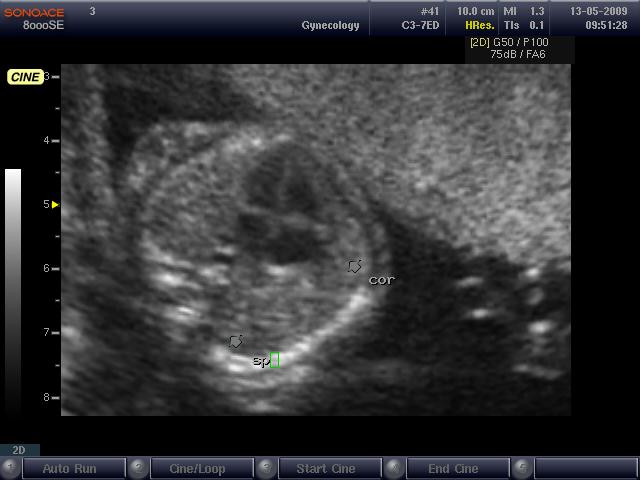

Медицинские специалисты подчеркивают важность ранней диагностики данного состояния с помощью ультразвукового исследования. Это позволяет оценить функциональность сердца и выявить возможные сопутствующие патологии. Лечение декстрокардии зависит от наличия других аномалий и может варьироваться от наблюдения до хирургического вмешательства. Врачи рекомендуют регулярные консультации с кардиологом и генетиком для обеспечения оптимального ведения беременности и здоровья ребенка.

| Диагностика у плода | Пренатальное УЗИ, эхокардиография плода. | Обнаружение сердца справа на рутинном УЗИ; Детальное исследование структуры сердца и крупных сосудов; Оценка расположения других органов брюшной полости. |

Подозрение на декстрокардию может возникнуть во время аускультации или пальпации при медицинском обследовании. Для более точной диагностики этого состояния могут быть использованы следующие методы:

- УЗИ и рентгенография сердца и сосудов;

- эхокардиография (ЭХОКГ);